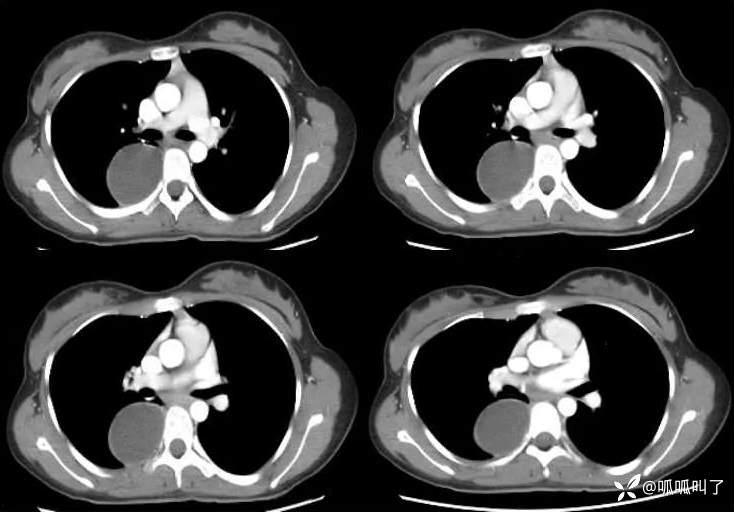

病史:女,17岁,高中学生,学校体检发现纵隔肿物,平素无明显不适症状,建议进一步检查,次日就诊于当地医院行胸部CT提示“右肺下叶脊柱旁占位”,建议入院治疗,后就诊于我院。

既往史:曾患先天性白内障并手术治疗。

CT